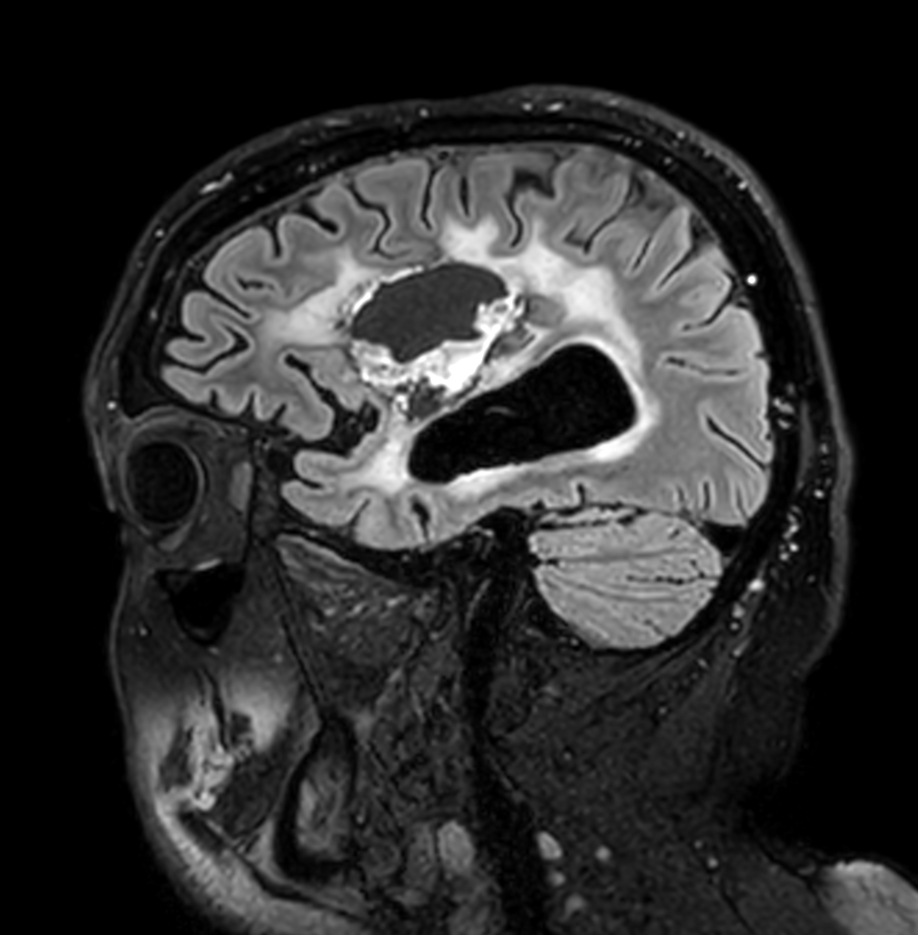

Brain glioblastoma, post-operative

Patient who was operated on glioblastoma

Sagittal 3D FLAIR